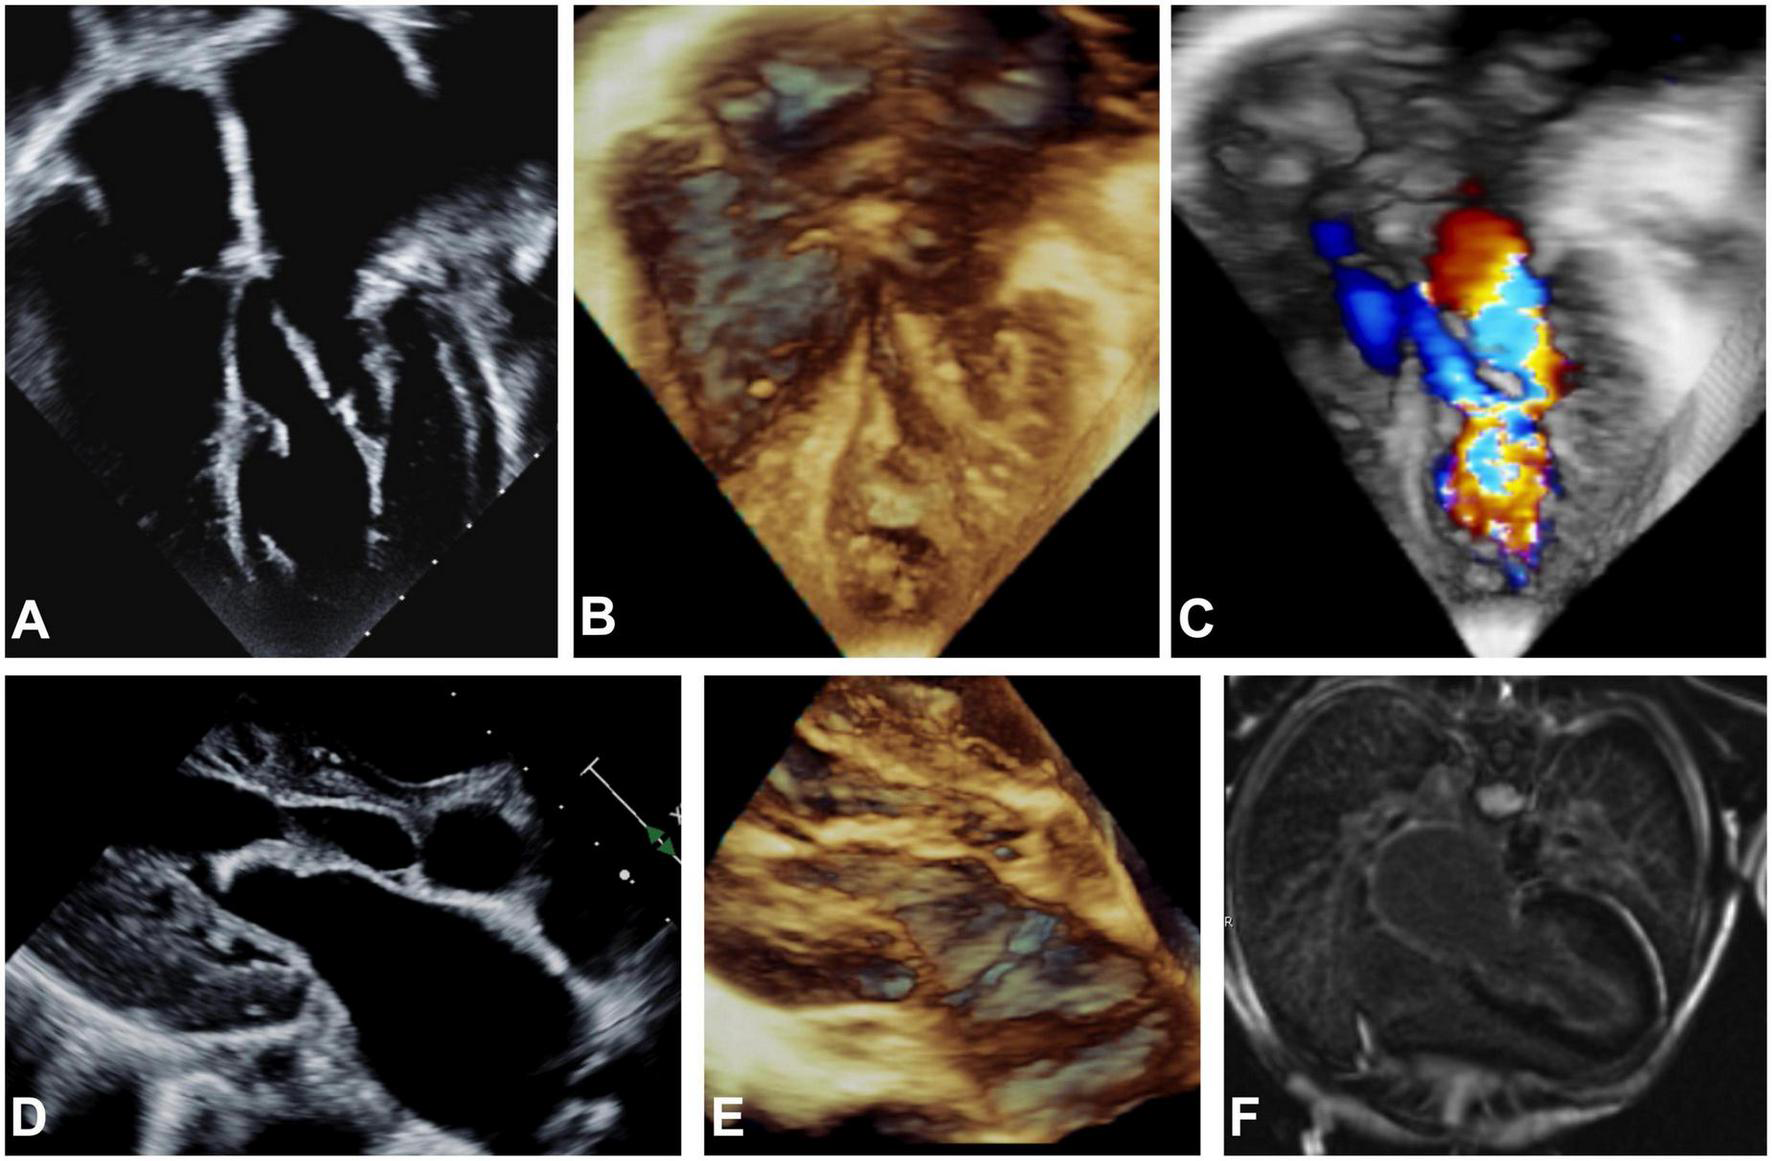

At 13 years old, the patient presented with an asymptomatic aortic valve gradient of 55 mmHg, which was reduced to 30 mmHg via balloon valvuloplasty. The pulmonary capillary wedge pressure was elevated to 21 mm Hg with a mitral stenosis mean gradient of 9 mm Hg. In the following year, the patient reported a steady decrease in energy levels, accompanied by leg numbness, and limited stamina even after short periods of rest. The patient was referred to our institution, and echocardiographic and MRI imaging revealed global LV hypertrophy and dysfunction. Thickened amorphic tissue with bright signals from the base to LV apex consistent with a diagnosis of EFE were detected on the endocardial LV surface involving the MV and subaortic region. Marked thickening of the atrial surfaces of the anterior and posterior MV leaflets in the mid leaflet region prevented effective leaflet coaptation (Figure 1). There was LVOTO (peak gradient if 45 mmHg, mean gradient of 22 mmHg), from the subaortic region extending to the undersurface of the bicuspid aortic leaflets. At repeat catheterization, LV filling pressures were increased to 20 mmHg. On cardiac CT, severe in-stent stenosis along nearly the entire length of the stented descending aorta was seen. Overall, the patient’s symptoms were attributed to an inability to significantly increase his cardiac output due to inflow and outflow obstruction and decreased diastolic compliance due to EFE.

FIGURE 1

Echocardiographic apical 4-chamber view (A–C), parasternal long axis (D,E) and MRI (F) imaging before EFE resection. 2D (A,D) and 3D (B,C,E) echocardiography showing hyperechogenic thickening of the endocardium on atrial, mitral valve, LV and LVOT level consistent with generalized EFE in the left sided structures of the heart is shown. Severe dilation of the left atrium can be noted. (C) Severe turbulences are detected by color Doppler in all left sided structures affected by EFE as compared to physiological color Doppler appearance in the right sided structures of the heart that are not affected by EFE. (F) Late gadolinium enhancement on endocardial level encapsulating all structures of the left atrium and ventricle is depicted.